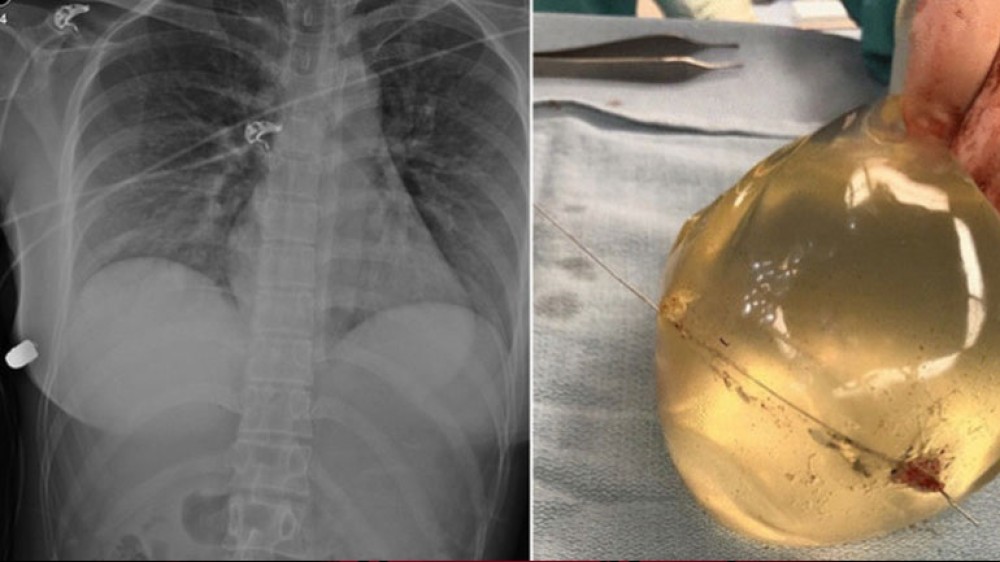

Οι χειρουργοί διαπίστωσαν ότι το τραύμα είχε μόνο μια είσοδο και εντόπισαν την σφαίρα κάτω από τον δεξιό μαστό της. Αφαίρεσαν τα εμφυτεύματά της και, όπως προκύπτει από φωτογραφίες που περιλαμβάνονται στη μελέτη και από τις αξονικές τομογραφίες στις οποίες υποβλήθηκε η γυναίκα, η σφαίρα πέρασε μέσω του αριστερού εμφυτεύματος και έπληξε το δεξί εμφύτευμα.

Όπως αναφέρεται στη μελέτη, “το αριστερό εμφύτευμα βρίσκεται πάνω από την καρδιά και την θωρακική κοιλότητα και τον πνεύμονα και έτσι είναι πιθανόν να έσωσε τη ζωή της γυναίκας”.